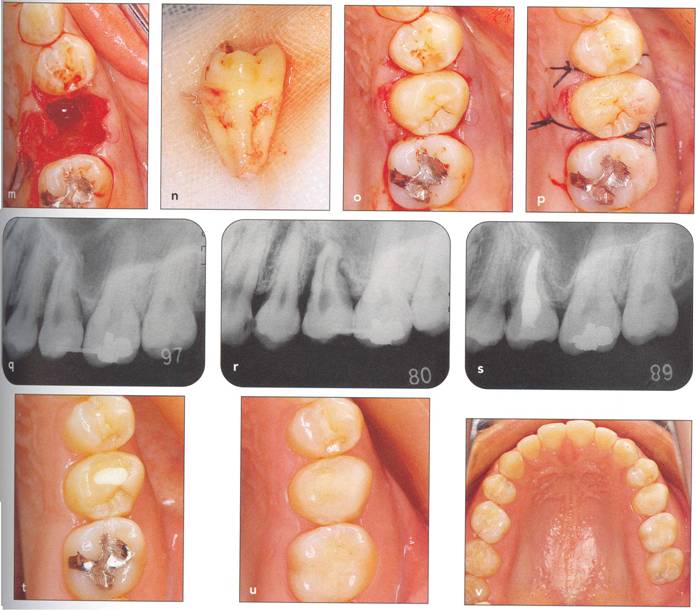

Fi 545e45f g 5-1f After extraction offirst molar from the recipient site. Fi 545e45f g 5-1 g The donor tooth. Note the adequate root form and amount of periodontal ligament on the root. Fi 545e45f g 5-1 h Measurement of the mesiodistal width of the donor tooth. |

Fi 545e45f g 5-1 i Measurement of the mesiodistal width of the recipient site. If the mesiodistal width of the donor tooth is greater than that of the recipient site, the proximal walls of the adjacent teeth are reduced to fit the donor tooth. Fi 545e45f g 5-1j Preparation of the recipient site. Removal of alveolar septum is done with a minirongeur. Fi 545e45f g 5-1 k After removal of the alveolar septum. |

Fi 545e45f g 5-11 Preparation of the recipient site with surgical round burs. Fi 545e45f g 5-1 m Prepared recipient site and extraction site of the donor tooth. Fi 545e45f g 5-1 n After transplantation of the donor tooth and suturing of the flap. |

Fi 545e45f g 5-10 Stabilization of the donor tooth. The donor tooth has been splinted to the adjacent tooth with twisted wire and selfcured composite resin after etching and bonding. Fi 545e45f g 5-1 p After transplantation. |

Fi 545e45f g 5-15 Three weeks after transplantation. Root canal therapy was started 2 weeks after transplantation. After temporary obturation with calcium hydroxide, the root canal was obturated with gutta percha in 5 weeks. Fi 545e45f g 5-1t Two and one half months after transplantation. |

Fi 545e45f g 5-1 u Definitive occlusal restoration of the donor tooth with composite resin. Fi 545e45f g 5-1v One year 3 months after transplantation. Normal periodontal ligament space and lamina dura are observed. |